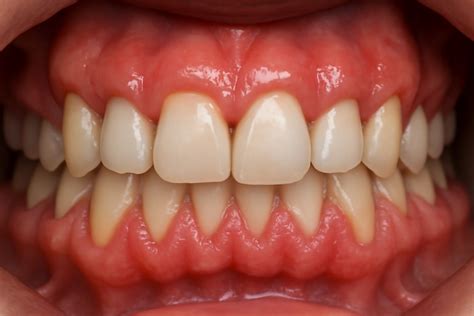

Hiperplasia gingival. No es propiamente una tumoración, pero puede llegar casi a ocultar los dientes (fig. 8). Presenta un aumento de las fibras colágenas y puede ocurrir sin una causa conocida o inducida por medicamentos, especialmente antiepilépticos (fenitoína) y ciclosporina, pero también verapamilo, nifedipino, diltiazem y otros muchos. Conviene diferenciarla también de la fibromatosis gingival hereditaria, los infiltrados en el curso de una leucemia y la hiperplasia gingival por falta de cuidados en la zona.